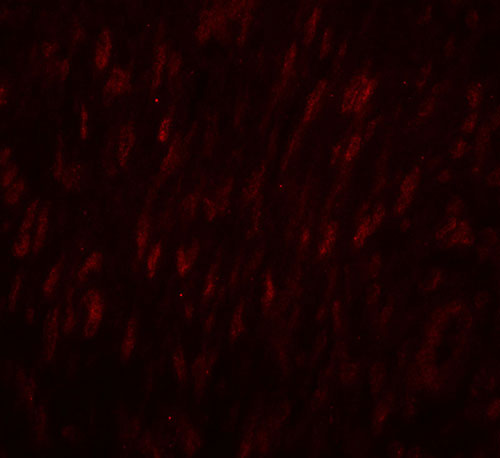

Immunofluorescence of SLC29A1 in human ovary tissue with SLC29A1 antibody at 20 μg/mL. |